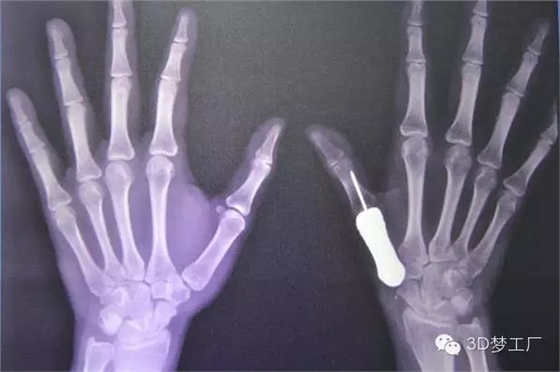

治療團隊一開始對病人健康的左手拇指進行掃描和拍攝X光片,然后用鏡像的方法渲染出她的右手拇指指骨原來應有的樣子,并用樹脂材料3D打印出其模型,最后用一種醫(yī)用鈦金屬鑄造出來。整個制造過程總共只用了一個星期左右,但是Phramongkutklao醫(yī)院骨科的醫(yī)生團隊為了研發(fā)這個3D打印拇指項目已經(jīng)耗費了將近兩年時間。

據(jù)了解,手術治療是從去年6月份開始的,當時醫(yī)生將惡化的骨頭從病人手里取出來,并等了一段日子以確保腫瘤不會復發(fā)。當這一情況在9月下旬確認之后,外科醫(yī)生繼續(xù)手術,植入鈦金屬指骨并將其與最近的肌腱連結在一起。